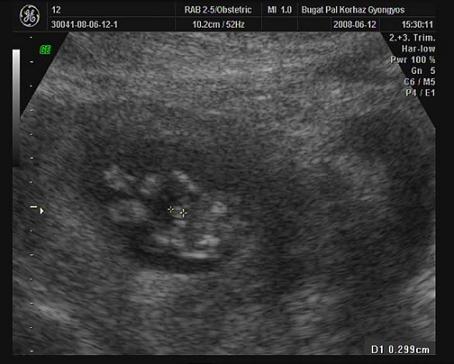

Dobok képet,mikor állítólag a kukiját mérte a doki! Édi nem? Párom erre csak annyit mondott, hogy reméli nöni fog!!!:lol: :oops:

Kép